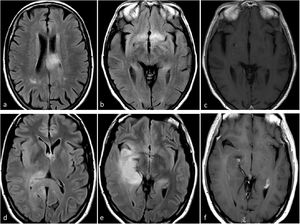

Astrocitoma IDH-mutado grado 2-3Estos dos grados histológicos suelen tratarse juntos debido a sus comportamientos similares18,59,61,62. La presentación más frecuente en las imágenes es una lesión infiltrante, sin o con escaso realce, con márgenes bien definidos y morfología nodular/ovalada. A pesar de una sensibilidad relativamente baja, el signo de mismatch T2-FLAIR muestra una especificidad casi perfecta en adultos (cuando representa, como mínimo, más de 25-50% de la extensión del tumor). El efecto de masa es más o menos escaso, así como el edema perilesional. No deben presentar indicios de necrosis en las imágenes4,23–27,38. En la DWI, la difusión puede variar entre facilitada y homogénea en el grado 2 y ligeramente heterogénea en el 3. No deben observarse elevaciones francas del CBV con la DSC-PWI34–36 (fig. 6). La ausencia de calcificación y de quistes, así como la morfología nodular/ovalada en lugar de un patrón giriforme siguiendo la corteza pueden ayudar en el diagnóstico diferencial con los oligodendrogliomas4,23–27.

Dos pacientes diferentes con características de imagen típicas de astrocitoma IDH-mutado grado 2-3. Sujetos de 31 (a-d) y 34 (e-h) años. Axial T2w (a y e), FLAIR (b y f), DWI (c y g) y mapas de color de CBV derivados de DSC-PWI (d y h). Masas redondeadas, bien definidas e hiperintensas en T2w con la correspondiente hipointensidad en FLAIR, con un fino borde periférico de hiperintensidad: signo de mismatch T2/FLAIR. Sin restricción significativa de la difusión en DWI y CBV bajo en los mapas de color de CBV.

CBV: volumen sanguíneo cerebral; DSC-PWI: imagen de perfusión dinámica; DWI: imagen potenciada en difusión; IDH: gen isocitrato deshidrogenasa.

Astrocitoma IDH-mutado grado 4Este subgrupo de astrocitomas con mutación de IDH ha sido menos estudiado en comparación con los grados 2-3, por lo que sigue suponiendo un gran desafío radiológico. Lamentablemente, estos tumores a menudo se agrupan (y, en consecuencia, están infrarrepresentados) con los de grados 2-3 dentro de la categoría más amplia de astrocitomas IDH-mutados. Sin embargo, esta agrupación generalizada puede ser contraproducente porque: 1) las diferencias entre los tumores IDH-mutados grados 2-3 y 4 son vitales para el manejo de los pacientes; y 2) la aplicación de estos indicadores de imagen en los grados 2-3 y 4 puede no arrojar resultados precisos para este último, que comparte características de imagen con los glioblastomas (del mismo grado histológico). De hecho, según las hipótesis, las imágenes de los astrocitomas IDH-mutados grado 4 se encuentran entre las de aquellos de grado 2-3 (con los que comparten la mutación IDH) y la de los glioblastomas sin mutaciones IDH (con los que comparten el grado histológico). Por lo tanto, según el grado histológico, este tumor debería presentar necrosis, restricción de la difusión y CBV elevado con frecuencia; no obstante, debido a la presencia de mutacion IDH debería manifestarse en pacientes menores de 55 años, estar bien definido y con una morfología nodular/ovalada. Además, recientemente se ha descrito la presencia de mismatch T2-FLAIR como específico también para el astrocitoma IDH-mutado grado 4. Si sumamos esto a los conocimientos previos, cabe pensar que un tumor con un mismatch T2/FLAIR que presenta focos de necrosis, realce prominente, restricción de la difusión o CBV elevado debería ser muy probablemente un astrocitoma IDH-mutado grado 465,66 (fig. 7).

Características de imagen en dos pacientes con astrocitoma IDH-mutado grado 4. a-c) Paciente de 37 años. Axial T2w, FLAIR y T1w poscontraste. Extensa lesión bien definida hiperintensa en T2w (a) con la correspondiente hipointensidad en FLAIR y delgado borde hiperintenso periférico en (b), consistente con el signo de mismatch T2/FLAIR que sugiere mutación en IDH. Se observa un pequño foco de realce y necrosis dentro del margen profundo del tumor (c), lo que sugiere un grado 4. Obsérvese también que, en este caso, una biopsia que no captara la necrosis podría subestimar el grado del tumor y considerarlo de grado 2-3. La detección de características de imagen de grado 4 dentro de un tumor con mismatch T2/FLAIR parece ser una manifestación específica de astrocitoma IDH-mutado grado 4. d-f) Paciente de 49 años. FLAIR axial (d), T1w poscontraste (e), y mapa de color de CBV derivado de DSC-PWI (f). Masa tumoral bien definida y redondeada en FLAIR (d) con áreas internas de realce sólido (e) dentro del tumor no captante. Pequeños focos de necrosis (flechas en e) y CBV claramente elevado (círculo en f). Cabe destacar que existía una necrosis más extensa en otras partes del tumor que no aparecen en esta figura. Un glioma con aspecto de grado 4 en un paciente menor de 55 años con algunas características atípicas para un glioblastoma, como una morfología redondeada clara y márgenes bien definidos, podría sugerir un astrocitoma IDH-mutado grado 4

CBV: volumen sanguíneo cerebral; DSC-PWI: imagen de perfusión dinámica; IDH: gen isocitrato deshidrogenasa.